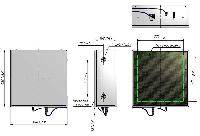

Мобильный рентгенаппарат + оцифровщик. Получение рентгеновского изображения на экране ноутбука. Вариант за 1,4 миллиона рублей под ключ.

Мобильный рентгенаппарат с печатью рентгенограмм на рентгеновской пленке. Цена 700000 рублей.